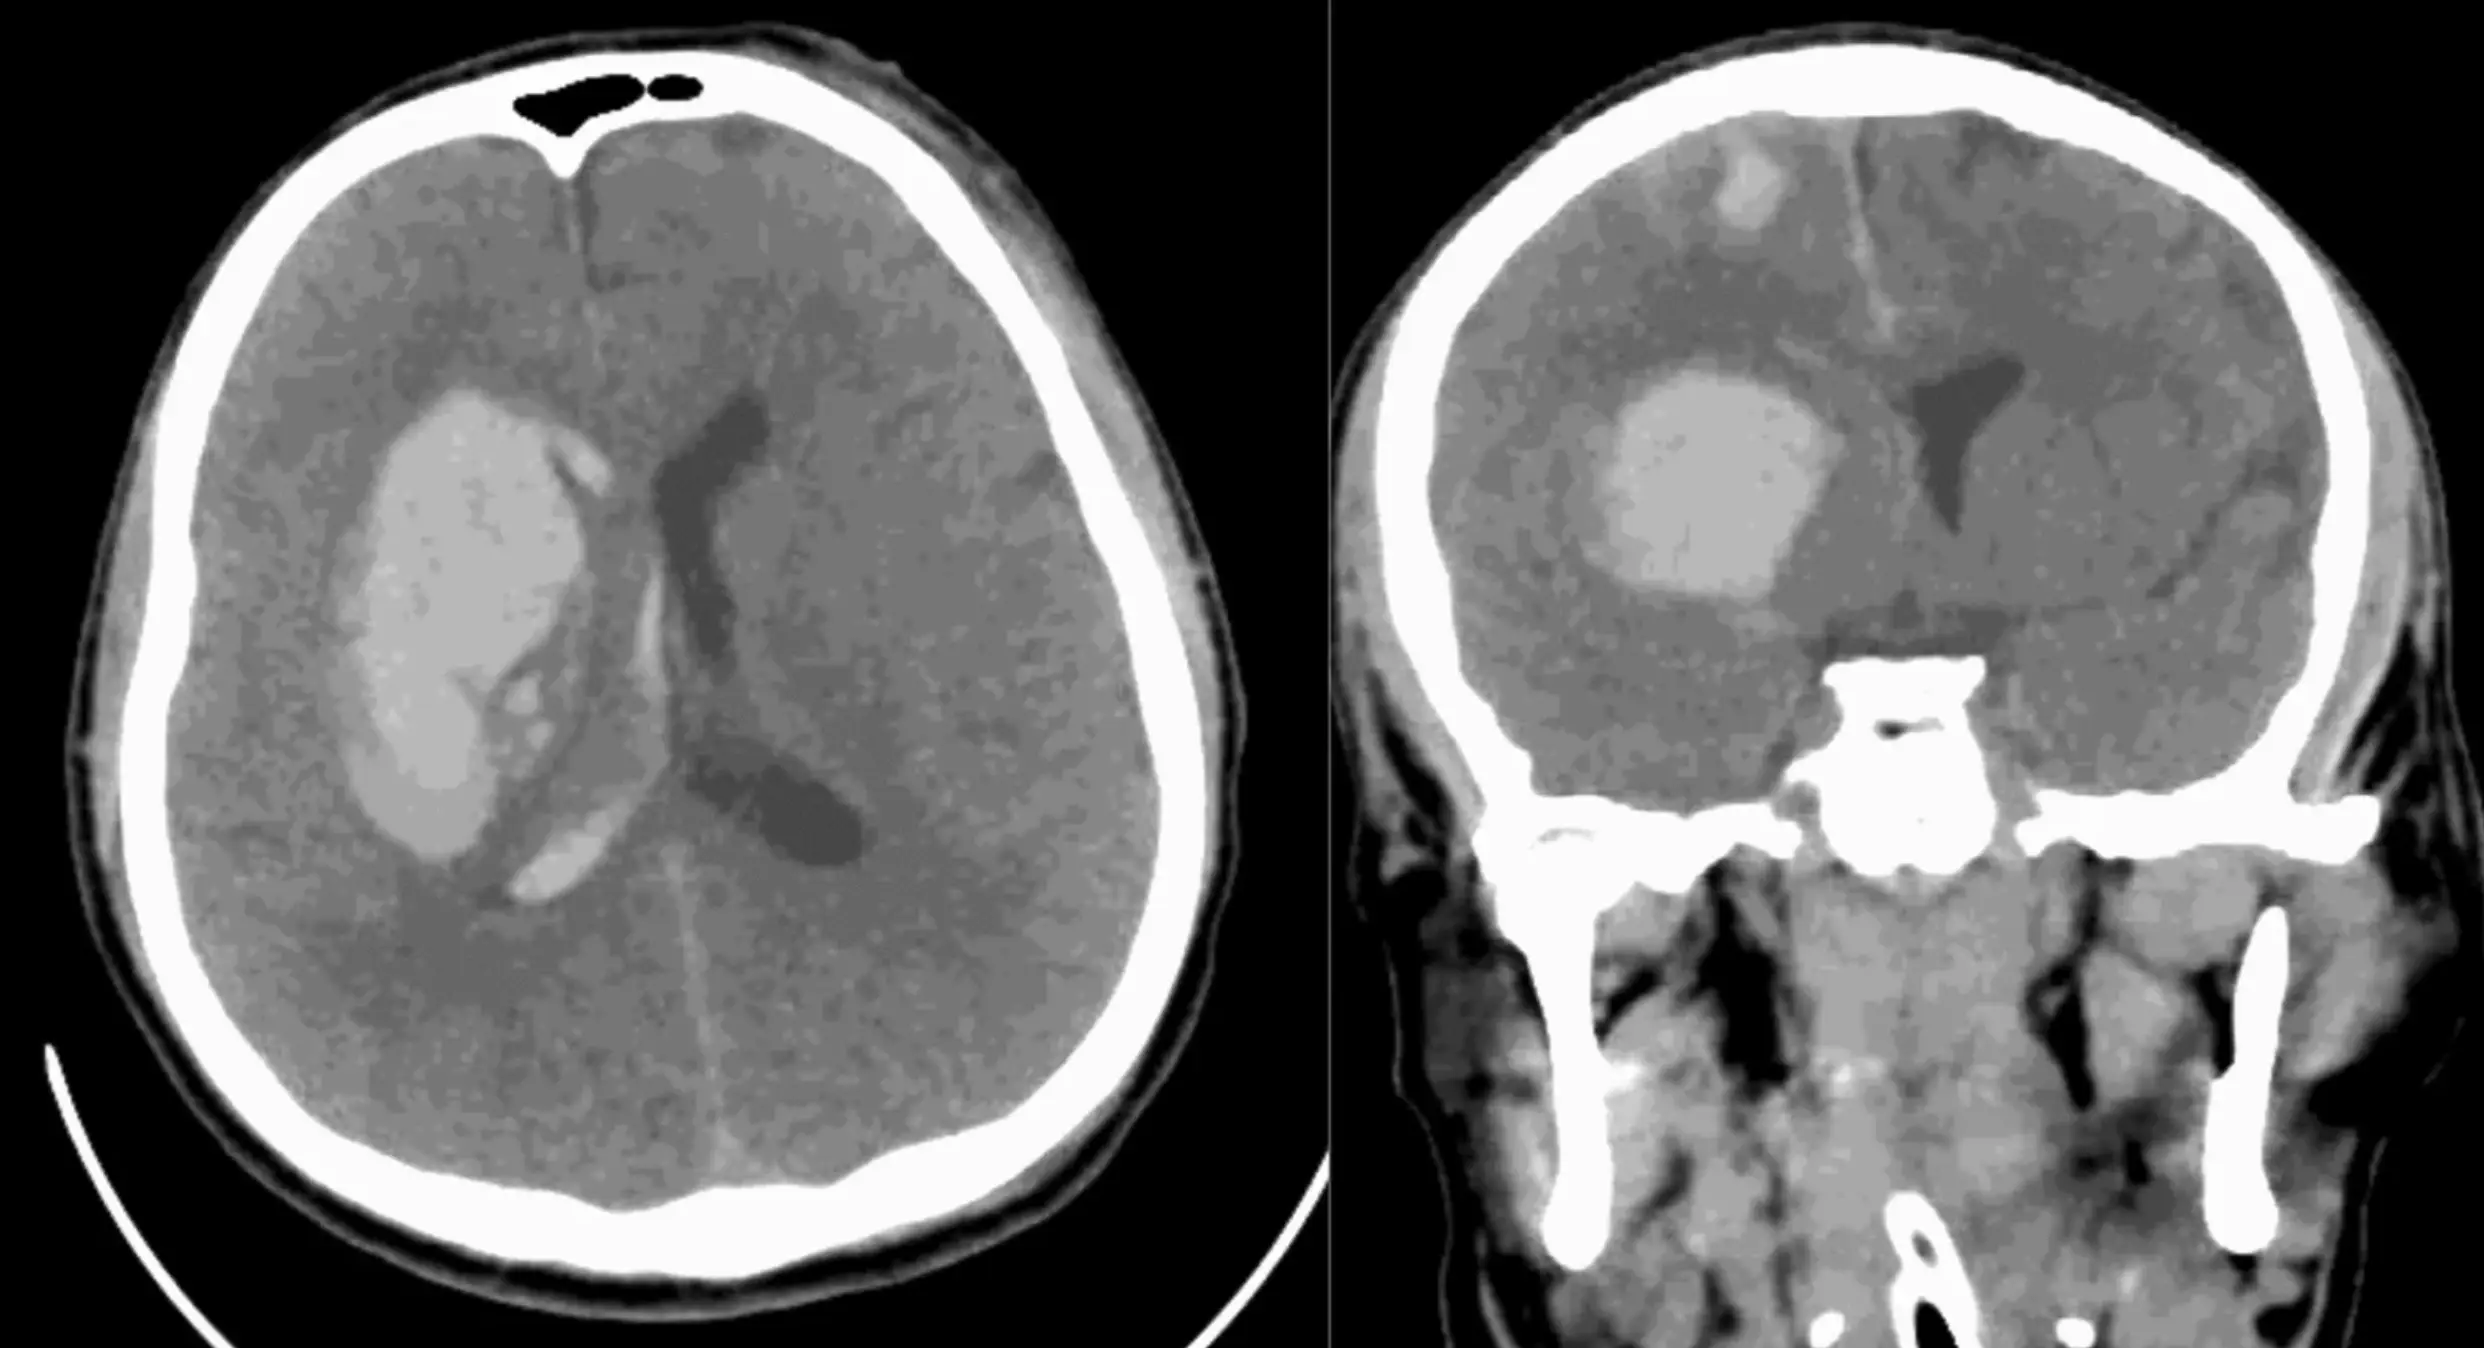

The drug-resistant fungus infected the 34-year-old just three months after suffering from a traumatic brain injury in a car crash.

He was treated in intensive care as medics dealt with bleeding from the mouth, a severe scalp laceration, and several cuts.

Part of his skull was removed to relieve pressure on his brain, but after further surgeries and antibiotic treatment, tests revealed that he had been infected with Candida auris.